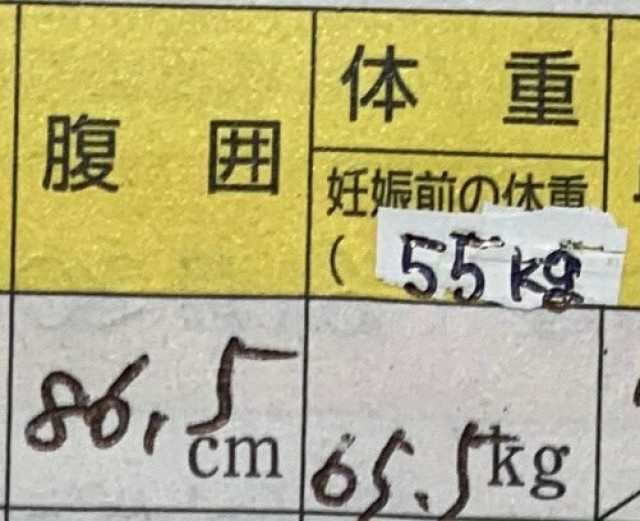

妊娠中の食事 無性に牛肉が食べたくなった昨日のランチ。妊娠してから、牛肉を食べたくなる回数がふえまました。産後ゆっくりと外食するのはだいぶ減ると思うので、今のうちに洋食屋さんでの食事をたのしんでおけて良かったです。 ※朝(妊娠前+6.6kg)

体重管理 中学生以来、 身長155cm デフォルト体重55kgの私。 久方ぶりの40kg台に興奮し思わず激写&赤裸々に披露! この数年は特に子どもの妊娠・出産で 53kg→73kg→51kg→63kg→53~58kg とかなり激しい体重変動がありました笑 ボイトレや体づくりをするようになって自然に落ちていったのがこれまた嬉しい。

体重管理 カレンダーに書くだけで、ずっとサボってた体重入力。やっとアプリに入れた〜! まともに体重をつけていなかった妊娠初期にガクッと減ったけど、最近は順調に増えてる⭕️

体重管理 32wでやっと!つわりで減った分を取り戻して妊娠前体重に戻った?長かった